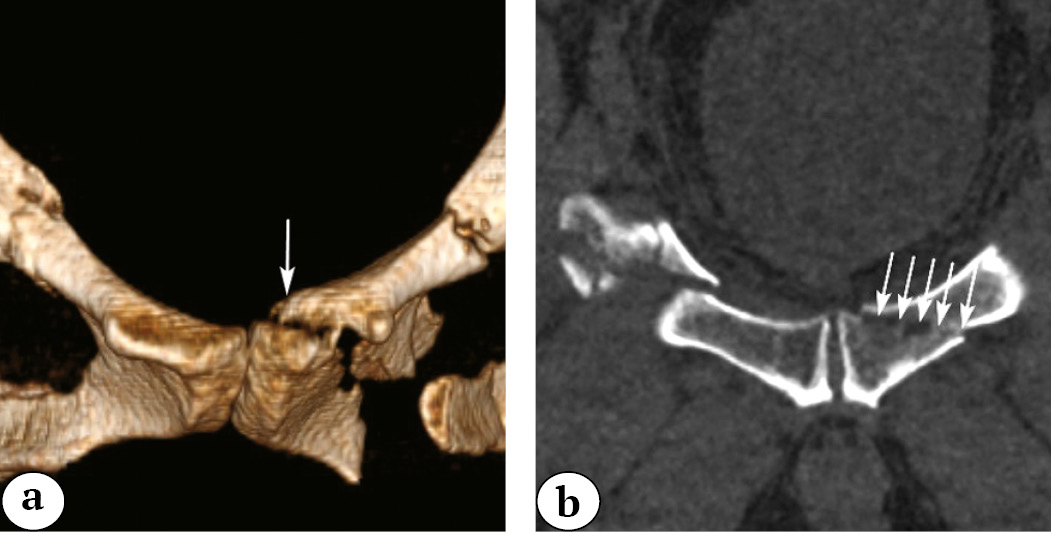

The drawback of such an approach is the absence of a commonly accepted Russian equivalent for the term “crescent fracture,” and it doesn’t take into account the degree of displacement of the fragments (subluxation, dislocation). In such situations, we suggest using the phrase “fracture-subluxation” or “dislocation of the ilium base” and specifying the degree of displacement of the ilium base fragment. For example, if there is a fracture with a displacement of less than 1 cm in the sacroiliac joint area, the injury can be described as a “fracture-subluxation of the ilium base” of type II (according to A. Day’s classification) (Fig. 8).

Fig. 8. 3D-CT image reconstruction of the pelvis, the inlet view. The arrows indicate the opening of the SIJ gap less than 1 cm

In another case, when there is a fracture with a displacement of more than 1 cm in the sacroiliac joint area, the injury can be described as a “fracture-dislocation of the ilium base” type II according to A. Day’s classification (Fig. 9).

Fig. 9. 3D-CT image reconstruction of the pelvis in the inlet view (a); 2D-CT image reconstruction of the pelvis in the axial view. Displacement of the fragments in the SIJ is greater than 1 cm. The arrow shows the level of the fracture of the iliac base in relation to the CPS, type II according to A. Day ( b)

However, when analyzing fractures in the area of the ilium base, we have encountered fractures that do not fit into existing classifications. For example, fractures that run along the entire base of the ilium without penetrating the sacroiliac joint. For such fractures, we propose our own term — “longitudinal fracture of the ilium base” (Fig. 10).

Fig. 10. Longitudinal fracture of the base of the iliac bone: a — 2D-CT image reconstruction in the axial view; b –3D-CT image reconstruction in the posterior view